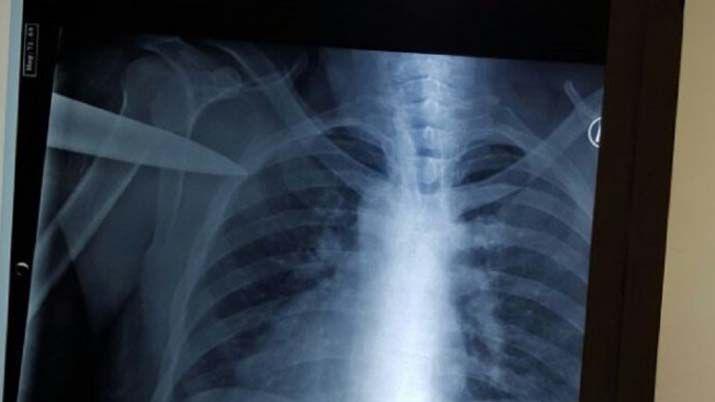

Al verlo, los médicos lo ingresaron y de inmediato le practicaron una placa para determinar la profundidad de la lesión y para chequear si había alguna herida de gravedad.

Por fortuna, el cuchillo no tocó ningún órgano vital. Luego fue intervenido quirúrgicamente y los médicos le extrajeron el puñal. A las pocas horas, fue dado alto.